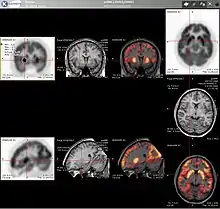

Neuroimaging

Neurology

PET imaging with oxygen-15 indirectly measures blood flow to the brain. In this method, increased radioactivity signal indicates increased blood flow which is assumed to correlate with increased brain activity. Because of its 2-minute half-life, oxygen-15 must be piped directly from a medical cyclotron for such uses, which is difficult.[16]

PET imaging with FDG takes advantage of the fact that the brain is normally a rapid user of glucose. Standard FDG PET of the brain measures regional glucose use and can be used in neuropathological diagnosis.

Brain pathologies such as Alzheimer's disease (AD) greatly decrease brain metabolism of both glucose and oxygen in tandem. Therefore FDG PET of the brain may also be used to successfully differentiate Alzheimer's disease from other dementing processes, and also to make early diagnoses of Alzheimer's disease. The advantage of FDG PET for these uses is its much wider availability. Some fluorine-18 based radioactive tracers used for Alzheimer's include florbetapir, flutemetamol, Pittsburgh compound B (PiB) and florbetaben, which are all used to detect amyloid-beta plaques, a potential biomarker for Alzheimer's in the brain.[17]

PET imaging with FDG can also be used for localization of "seizure focus". A seizure focus will appear as hypometabolic during an interictal scan.[18] Several radiotracers (i.e. radioligands) have been developed for PET that are ligands for specific neuroreceptor subtypes such as [11C]raclopride, [18F]fallypride and [18F]desmethoxyfallypride for dopamine D2/D3 receptors; [11C]McN5652 and [11C]DASB for serotonin transporters; [18F]mefway for serotonin 5HT1A receptors; and [18F]Nifene for nicotinic acetylcholine receptors or enzyme substrates (e.g. 6-FDOPA for the AADC enzyme). These agents permit the visualization of neuroreceptor pools in the context of a plurality of neuropsychiatric and neurologic illnesses.